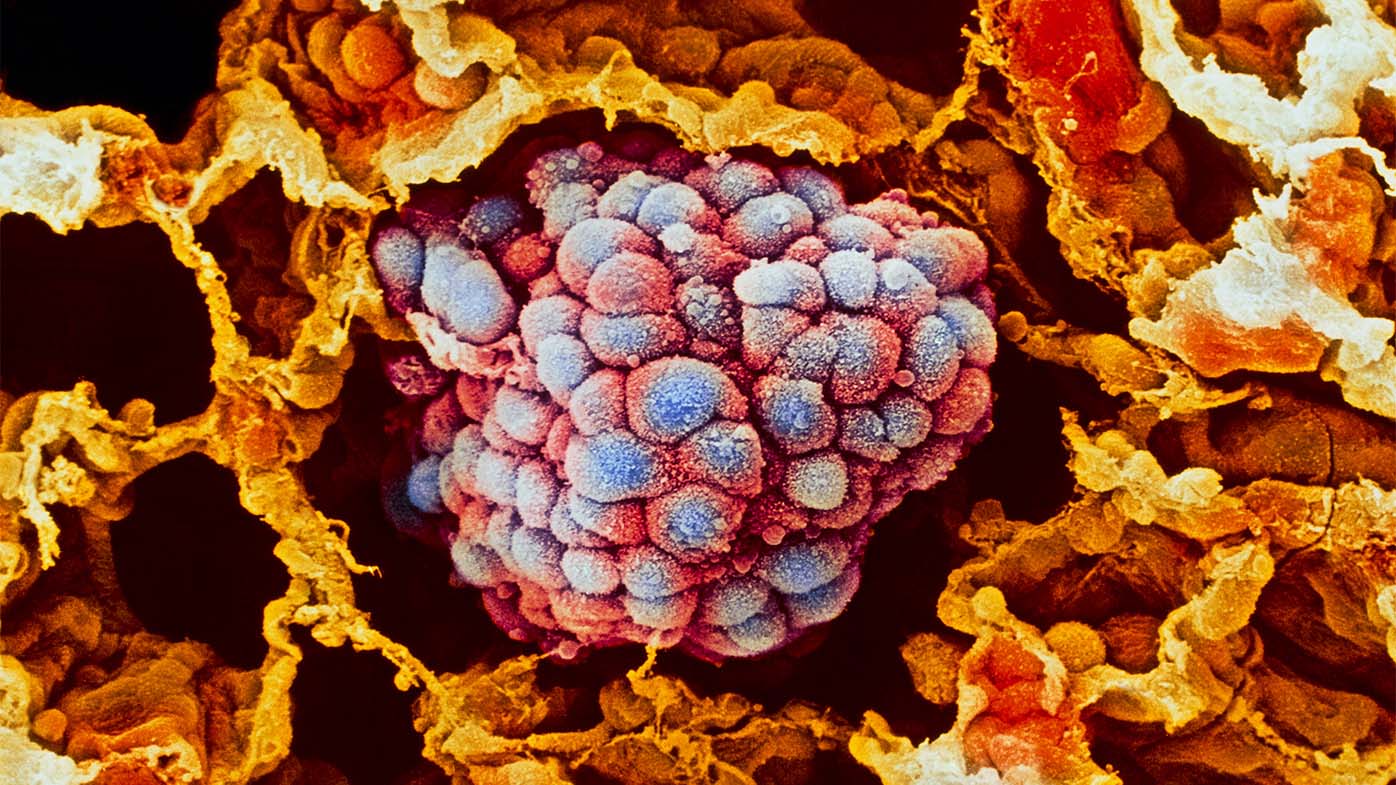

Раковая шишка – это заболевание, которое поражает кожу и слизистые оболочки. Она может возникнуть в различных частях тела и иметь различные внешние проявления. В данной статье мы представляем вам многочисленные фотографии раковых шишек, чтобы вы могли узнать, как они выглядят.

Одной из наиболее распространенных локализаций раковых шишек является лицо. На фото вы можете увидеть различные типы раковых шишек, такие как базалиома, плоскоклеточный рак и меланома. Обратите внимание на характерные признаки каждого типа раковой шишки, такие как изменение цвета, формы и размера.